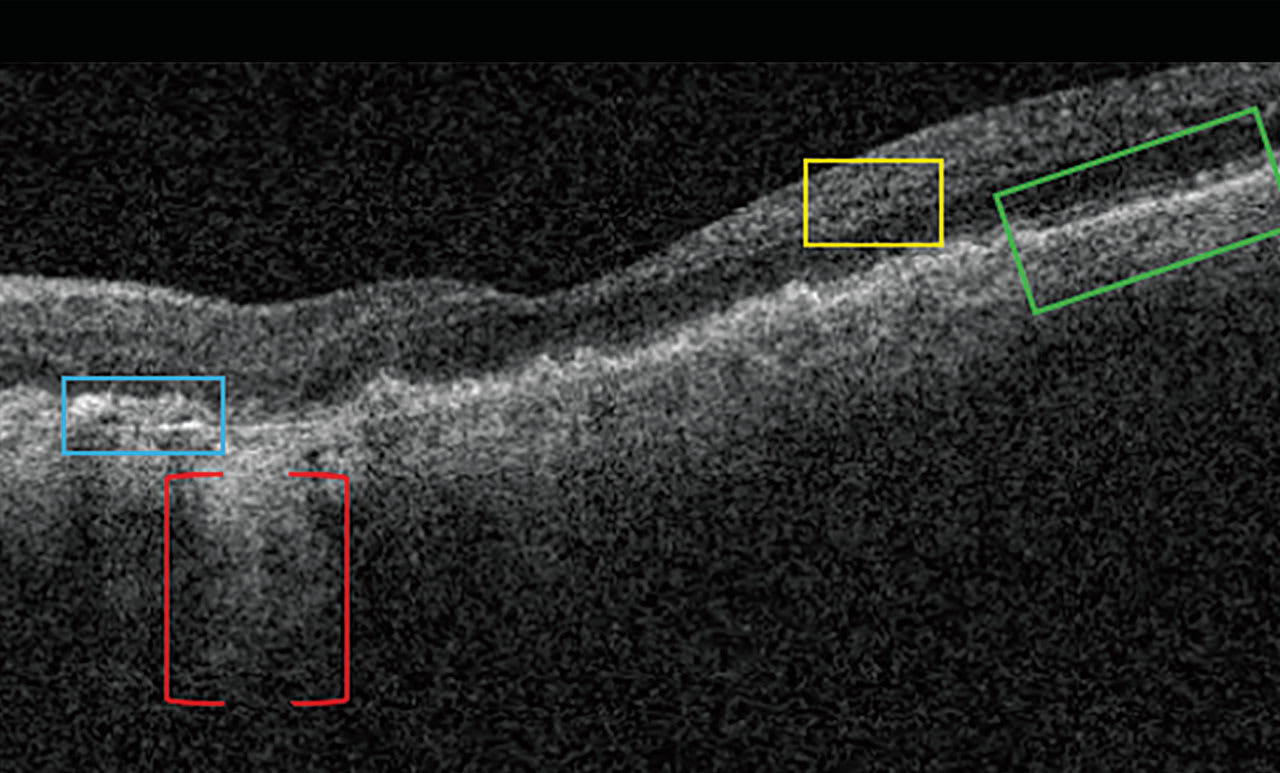

Nascent GA is drusen-associated incomplete RPE and outer retinal atrophy (iRORA) without CNV.1,2 On OCT, it appears as a subsidence of the outer plexiform layer (OPL) and the inner nuclear layer (INL), along with a wedge-shaped band within the OPL.1 The lesion’s boundaries are defined by “an abrupt increase in choroidal reflectivity below Bruch’s membrane; the RPE, photoreceptor, and choriocapillaris layer loss; and external limiting membrane absence/descent”.1 Also, nascent GA and iRORA increase progression risk to GA. In fact, eyes that have some of the findings of iRORA are at high risk of developing advanced AMD3 (Figure 2).

On OCT, drusen appear as RPE elevations. Calcified drusen have a hyporeflective core surrounded by a hyperreflective area on OCT (Figure 3). Patients who have heterogeneous internal reflectivity within drusen (HIRD) have a 6-fold risk of progressing to advanced AMD within a year.4

Reticular Pseudodrusen and Subretinal Drusenoid Deposits Reticular pseudodrusen (RPD), also called subretinal drusenoid deposits (SDD), are anterior to the RPE layer and have a reticular pattern of yellow-white lesions on CFP. RPD are associated with multifocal GA lesion development.1 On OCT (Figure 3), RPD are hyperreflective above the RPE (drusen are below the RPE). Patients who have RPD have a 2-fold increased risk of progressing to advanced AMD.5

IHRF are small, punctate structures that are hyperreflective on OCT. They are mostly located in the INL and OPL. Patients with IHRF are at risk of developing GA within 2 years by 5-fold (see “Comparing Biomarker Progression Risks,” below).6